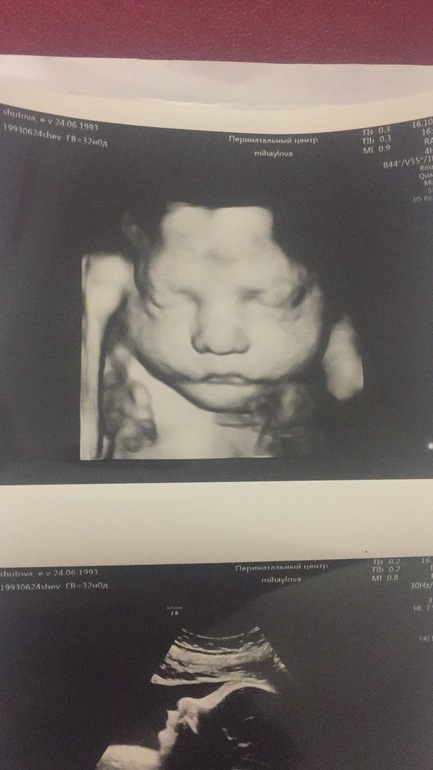

Ну и фото моей малышки) Копия сына))

По УЗИ нет проблем.

Булочка моя 2000 кг +382 гр под вопросом.

Что шокировало : шейка 50 мм.

Рубец 5,6. Узисты обалдели.

Я не планировала фото делать, узист не удержалась и сама предложила 3д)

Фото малышки просто прелесть 🥰 будущая модель))) умеет позировать)))